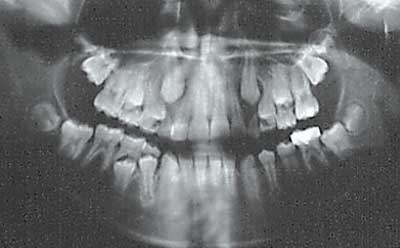

No hubo recurrencia de imágenes radiolúcidas en ninguna de las radiografías postquirúrgicas durante el seguimiento periódico de los pacientes. Tres (3) pacientes fueron seguidos por 7 años y uno de ellos tenía la lesión más abajo de la región cervical del primer molar inferior permanente no erupcionado y ahora está completamente en oclusión pero tuvo que ser ayudado con ortodoncia. (PACIENTE #1)

Cuatro (4) pacientes fueron evaluados por 5 años, dos (2) pacientes por 3 años 9 meses y tres (3) pacientes por 2 años y 6 meses. Todos los casos mostraron buena formación ósea alrededor del diente involucrado con la lesión y completa erupción de la dentición permanente. Los dientes erupcionados mostraron adecuada vitalidad pulpar y llegaron a ocluir correctamente. Dos (2) de los pacientes necesitaron tratamiento ortodóncico para corregir su maloclusión sin extracciones.

Foto 9: Rx Post 07-2005

Foto 10: Rx Post 02-2006